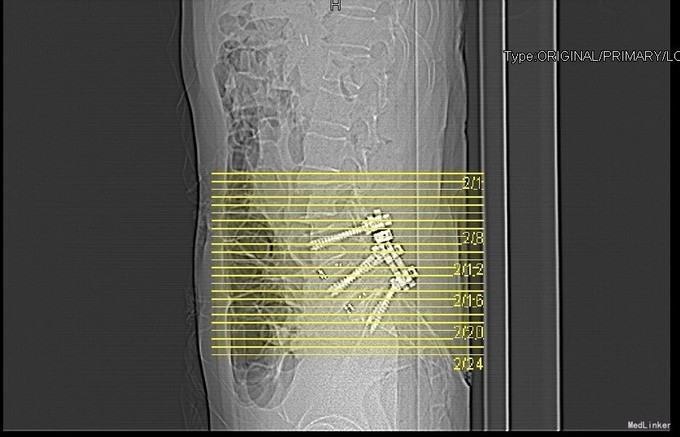

主诉:反复腰部疼痛20+年,加重伴双下肢胀痛麻木 现病史:患者于20+年前,因车祸行腰椎检查发现腰4椎体I°滑脱,并感腰部阵发性隐痛不适,一直未行特殊处理、4月前患者感腰部疼痛有所加重,并感双下肢阵发性胀痛麻木,久坐或弯腰后症状加重,以左下肢为甚,症状明显时难以直立行走,不伴畏寒发热、潮热盗汗等不适。10+天前患者在院外行理疗(具体不详),上述症状略有好转。在院外行腰椎x光摄片诊断为"腰4椎体II°滑脱,腰5椎体I°滑脱",故来我院就诊,门诊以"腰椎滑脱"收入住院

查体:脊柱外观无侧弯后突畸形,双下肢无肌肉萎缩。腰4-5、腰5骶1棘上棘旁轻压痛,伴左侧下肢放射;会阴部感觉未见异常,双侧小腿前外侧及足背足底感觉减退。腰椎前屈后伸及侧屈活动度正常;双下肢髂腰肌肌力4级,左侧直腿抬高试验阳性,加强试验阳性,左侧膝腱反射减弱,双侧病理征未引出。 辅助检查:院外腰椎正侧位片:腰4椎体II°滑脱,腰5椎体I°滑脱。

诊断:腰4椎II°滑脱症,腰5椎I°滑脱症 治疗:经后路腰4、5椎切开复位、椎管减压、Capstone椎间及后外侧人工骨+自体骨植骨融合、Legacy内固定术